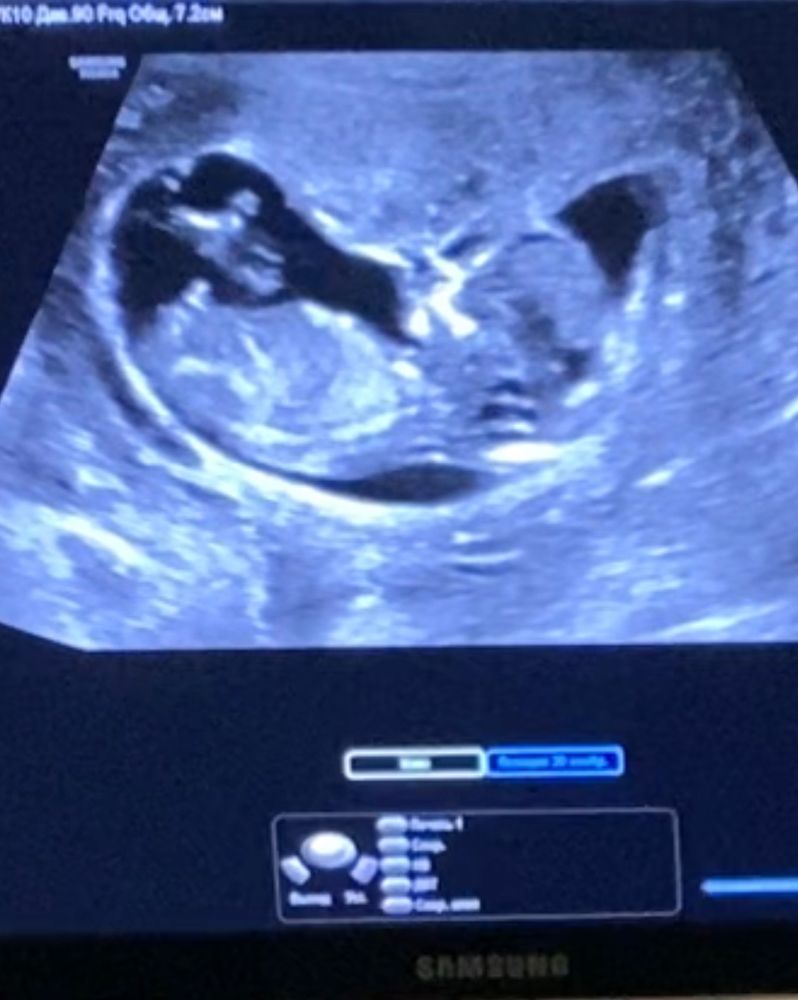

Девушки, мы больше года планировали с мужем беременность. Заказала тесты на вб, вчера сделала один. Показал сразу положительный, но в отзывах на ВБ пишут что часто реагент. Ночь не спала из-за мыслей, бегала в туалет до 3 ночи. Сегодня в 8 утра сделала остальные тесты, что оставались. Сдала кровь на хгч, но результат будет в понедельник аж( сего